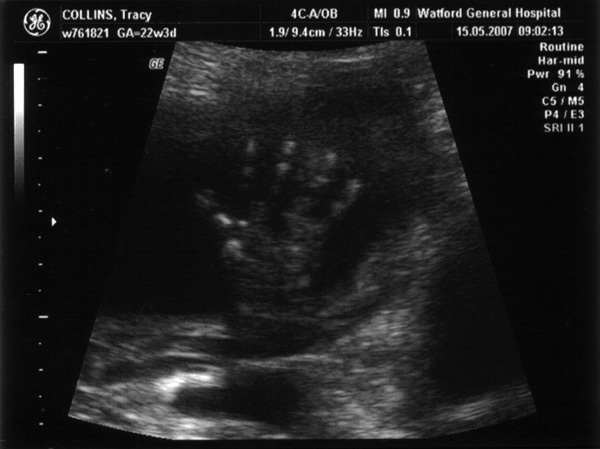

Third scan, 15th May 2007, (21 weeks)